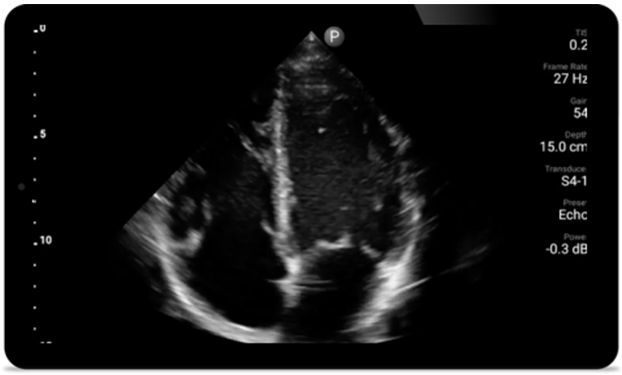

Every second counts in cardiac care

Heart attack patients need immediate care. Lumify's cardiac presets can help patients get diagnosed faster to improve their outcomes.

Lumify S4-1 broadband phased array transducer

• 4 to 1 MHz extended operating frequency range • 2D, color Doppler, M-mode, advanced XRES and multivariate harmonic imaging • High-resolution imaging for abdominal and cardiac applications: Cardiac, OB/GYN, Lung, Abdomen and FAST imaging preset optimizations Lumify aids life-saving technology in prehospital setting